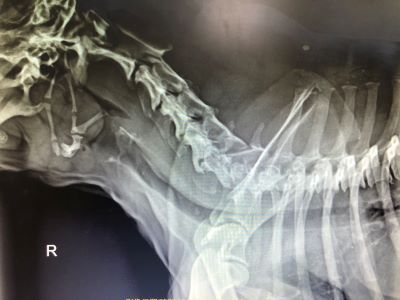

12歲未絕育男生 峽谷㹴主訴近幾周內喘 越來越嚴重 在附近看了四間不同間醫院都無法處理而轉來本院

初步懷疑呼吸道阻塞,安排電腦斷層掃描/內視鏡探查手術,精準定位病灶團塊的範圍,